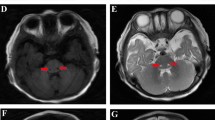

In order to make a positive diagnosis, auxiliary examination was applied. Blood gas analysis of patient 1 was pH 7.29, PaCO2 27 mmHg, Pa02 179.5 mmHg (Fi02 40%), HC03−12.8 mmol/L, and BE-15.5. Anion gap (AG) was 32.3, suggesting a high degree of AG metabolic acidosis. Routine blood test, C-reactive protein (CRP), and cerebrospinal fluid lactic acid were normal, excluding the existence of central nervous system infection. Biochemical result was as follows: alanine aminotransferase 88 U/L, albumin 27.5 g/l, urea nitrogen 17 mmol/L, uric acid 882.2 umol/L, blood lactate 5.2 mmol/L (normal 1.0 ~ 1.7 mmol/L), and troponin 0.26 ng/m L. Blood ammonia was 96 mmol/ L, argued the possibility of hyperammonemia. Echocardiography showed right heart enlargement and pulmonary hypertension. Thoracic and abdominal plain X-ray and CT scanning demonstrated pulmonary hypertension and ascites. Urinary organic acid analysis displayed mild phenylketonuria combined with mild methylmalonic aciduria. Skull CT demonstrated decreased symmetry density of bilateral white matter, indicating the presence of leukoencephalopathy Fig. 1a. Cranial MRI revealed extensive signal abnormalities in the subcortical white matter of both cerebral hemispheres, with bilateral internal capsule, external capsule, corpus callosum, and medulla involved. MR diffusion-weighted imaging (DWI) sequences showed limited value of diffusion, illustrating active pathological process period (Fig. 1b).

Extensive signal abnormalities (a, b patient 1; c, d patient 2) illustrated by imaging examination. Symmetrical low density (a) and T2WI high signal (b) are found in bilateral periventricular region with corpus callosum and semioval center affected. Head MR (c) and DWI (d) demonstrated abnormal signals across medulla, midbrain, thalamus, lateral ventricle, and centrum ovale

Patient 2 presented similar clinical manifestations. Routine blood test, CRP, and cerebrospinal fluid lactic acid were generally normal. Blood ammonia was 23.5 umol/L, eliminating the existence of hyperammonemia. Cerebrospinal fluid virus detection was negative therefore central nervous system infectious diseases were excluded. Urinary organic acid analysis showed increase of pyruvic acid, lactic acid, and 3-hydroxy butyric acid, suggesting ketonuria. CT illustrated abnormal signal in frontotemporal portion, excluded eripheral hydrocephalus and brain growth retardation. Head MR and DWI demonstrated abnormal signals across medulla, midbrain, thalamus, lateral ventricle, and centrum ovale (Fig.1c, d). In line of the results, the sufferers were with energy metabolism disturbance and suspected as metachromatic leukodystrophy.